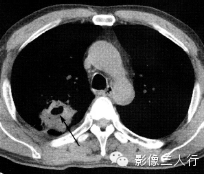

| 肺脓肿(图1) | 肺结核空洞(图2) | 癌性空洞(图3) | |

| 空洞形态 | 洞壁厚、模糊,内壁较光滑,内多见液平面 | 洞壁薄、内壁较光整,周围常有卫星灶 | 洞壁厚,多呈偏心性增厚,内壁常呈结节状 |

(B)平扫纵隔窗